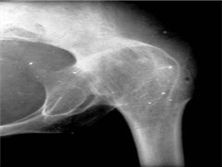

骨感染感染病包括:骨雅司病、骨包囊虫病、骨放线菌病、布氏杆菌病、骨及关节梅毒等疾...

骨关节及软组织CT、X线平片